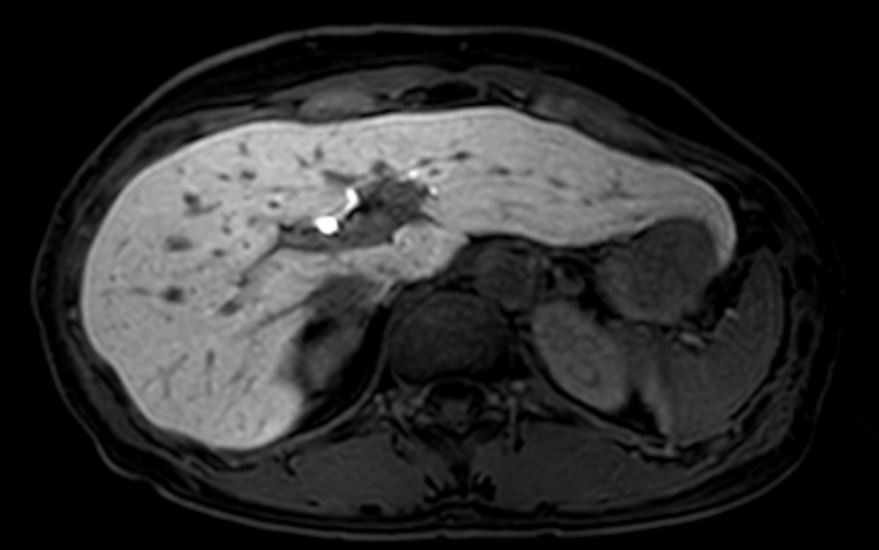

- CT/MRI: 의심 병변 정밀 확인